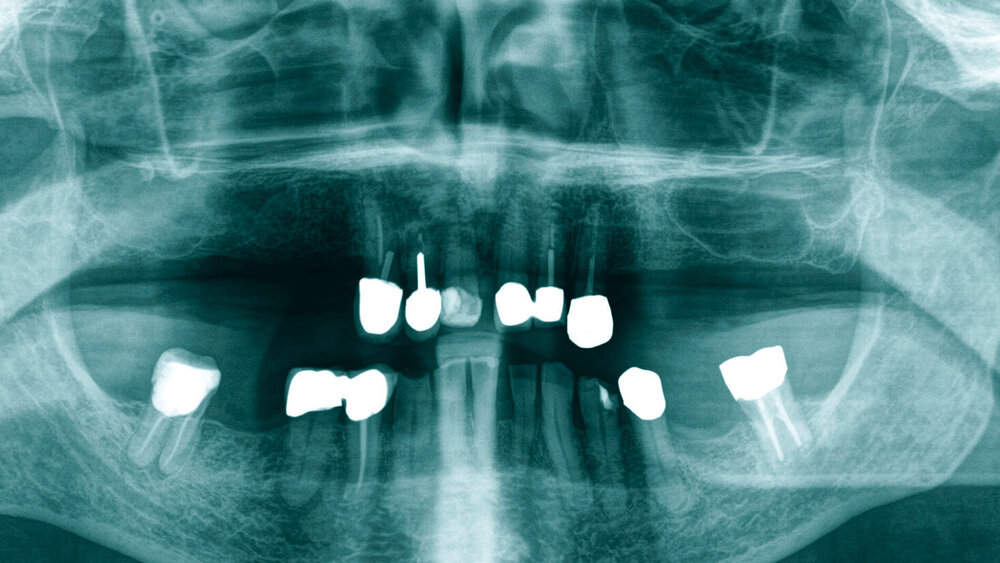

Die klinische Symptomatik, verbunden mit der radiologischen Auffälligkeit einer apikalen Osteolyse, legte den Verdacht nahe, dass es sich um eine akute Exazerbation einer chronisch-apikalen Ostitis an Zahn 47 handelt, und der Patient wurde über die Notwendigkeit einer Wurzelspitzenresektion aufgeklärt (Abbildung 1). Auf seinen ausdrücklichen Wunsch erfolgte allerdings am gleichen Tag die komplikationslose Zangenextraktion des Zahns.